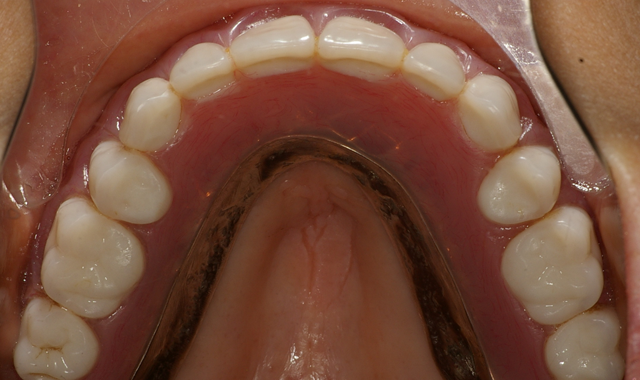

After a total of about three minutes, the overdenture with the incorporated retention caps was removed (Fig. 12). Any excess material was removed with a trimming bur (Fig. 13). At the completion of the prosthetic phase, the patient stated how pleased she was to be able to smile and function without the prosthesis wobbling or falling out (Fig. 14).

Fig. 13 Fig. 14

Today, we’re seeing more and more patients presenting to the dental practice with dentures that are unstable, loose and uncomfortable. By offering cost-effective treatment options - such as overdentures with dental implants when there’s minimal bone support - function and esthetics can be delivered efficiently and effectively.